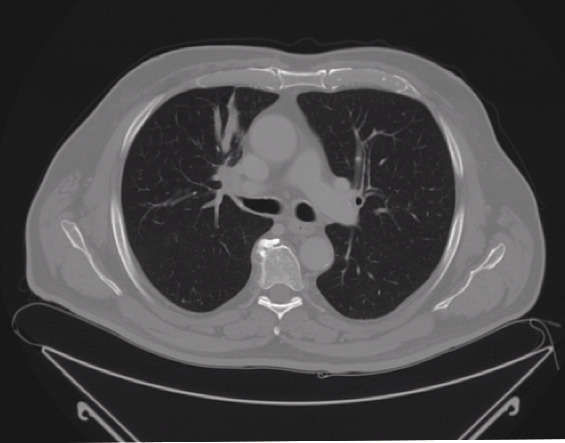

Alla luce del dato diagnostico ottenuto, il caso viene quindi discusso per definire il miglior approccio terapeutico e viene posta collegialmente indicazione al trattamento chemioterapico con intento neoadiuvante secondo lo schema cisplatino e docetaxel, con rivalutazione di malattia dopo 3 cicli, che il paziente ha eseguito in assenza di effetti collaterali di grado moderato-severo, esclusa l’alopecia completa e fatta eccezione per la neutropenia di grado 3 (870 neutrofili/mm3 totali) al nadir del secondo ciclo, non febbrile, che non ha richiesto alcuna terapia profilattica domiciliare. Il paziente ha inoltre segnalato nausea di grado 1 nei due giorni successivi alla somministrazione dei farmaci del primo ciclo e una progressiva astenia a decorrere dal secondo ciclo di trattamento sino a un massimo di grado 2, protrattasi poi fino al termine del terzo ciclo. L’esame TC torace, addome superiore e cranio con mezzo di contrasto di rivalutazione ha evidenziato una risposta parziale al trattamento (secondo i criteri RECIST 1.1) (Figura 3) [8], conseguendo una riduzione dimensionale delle linfoadenopatie ilo-mediastiniche e della lesione primitiva in misura superiore al 30%.

Figura 3. Ristadiazione mediante TC dopo 3 cicli di trattamento neoadiuvante